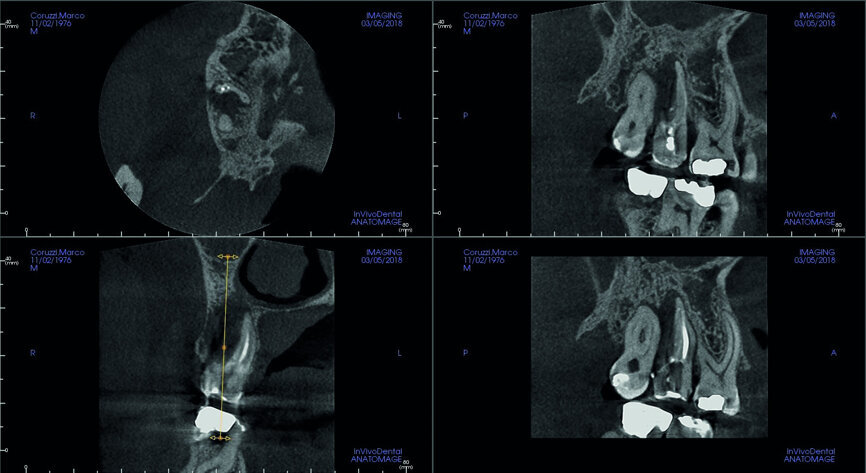

Fig. 5: Pre-op CBCT scan, sections.

Fig. 6: Pre-op CBCT scan, detailed section of the maxillary second molar.

A 47-year-old male patient in a good medical condition and a non-smoker was referred to our dental practice for endodontic retreatment of the right maxillary second molar. The dental history revealed that the tooth had been endodontically treated three months before because of acute pulpitis. After the treatment, the patient complained of pain on chewing. Antibiotics and a non-steroidal anti-inflammatory drug were prescribed, but the pain remained. After a month, a sinus tract appeared. The tooth was retreated in another practice without success. The clinical inspection revealed the presence of a sinus tract near the apical region of tooth #17. The tooth had been prepared for a full crown, but was without even a temporary crown, and the access cavity had been closed with temporary filling material. Cracks were evident on the buccal and mesial surfaces. Periodontal probing showed a deep pocket (> 12 mm) on the distal aspect of the root trunk (Figs. 1 & 2). The periapical radiograph showed a radiolucency between the roots of the second and third molars. The radiographic appearance of the endodontic treatment was good, without clear evidence of periapical radiolucencies (Fig. 3). A perforation of the pulp chamber floor was suspected. A CBCT scan was performed (Figs. 4–7), and it confirmed the suspicion of perforation, along with the presence of a large periradicular radiolucency and an unfavourable root shape.